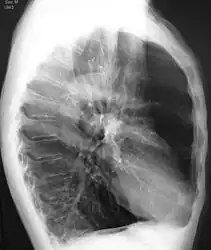

- Chest X-ray demonstrating severe COPD: Note the small heart size in comparison to the lungs.

- A lateral chest X-ray of a person with emphysema: Note the barrel chest and flat diaphragm.